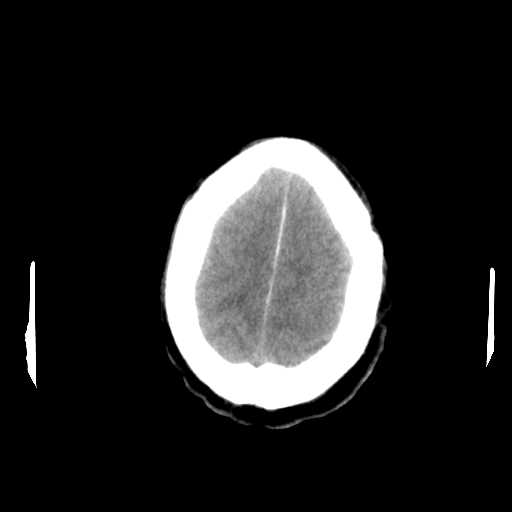

Figure 1: Illustrative examples of different types of brain hemorrhages in CT scans. The hemorrhagic regions are highlighted in red. (a) IPH, (b) IVH, (c) EDH, (d) SAH, (e) SDH.

The dataset used in this study was collected from two medical centers in Tehran, Iran: Rasoul Akram Hospital and Firouzabadi Hospital, over a period spanning 2018 to 2024. All CT scans were manually labeled hierarchically by two board-certified neurosurgeons to ensure accurate classification of ICH subtypes. The labeling process involved an initial annotation by one neurosurgeon, followed by validation and verification by a second expert to minimize errors and inconsistencies. Fig. 1 illustrates representative examples of different ICH subtypes in brain CT scans. The hemorrhagic regions are highlighted in red for better visualization. These annotated examples provide insight into the distinct imaging characteristics of each hemorrhage type, emphasizing the variability in their locations and appearances within the brain. The study received ethical approval, and data collection was conducted in compliance with institutional review board (IRB) regulations and the Declaration of Helsinki, ensuring patient confidentiality and adherence to ethical standards.